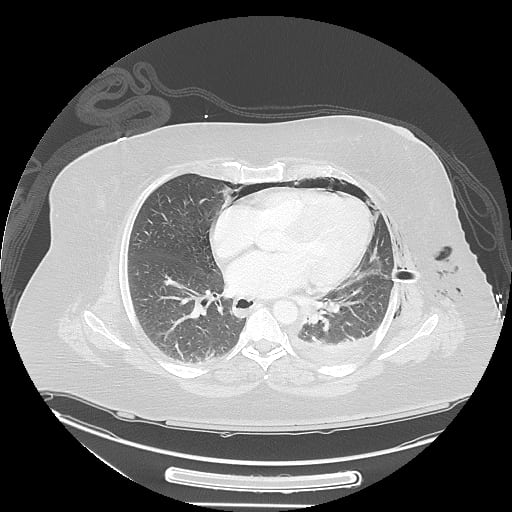

Sample ReportPneumopericardium.

Multiple left posterior rib fractures with a small left pneumothorax. No mediastinal shift.

Query lucency outlining the right hemidiaphragm, which could represent pneumothorax layering anteriorly on this supine radiograph. Consider CT for further assessment.

Asymmetric hazy opacification of the left hemithorax, which may represent a layering pleural effusion. No focal airspace opacification.